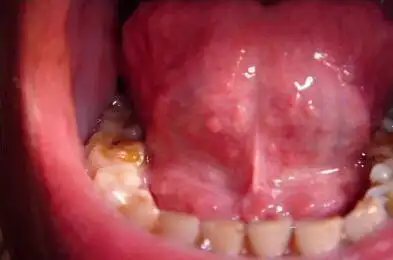

尖锐湿尤图症状图片男(尖锐湿疣有哪些症状?